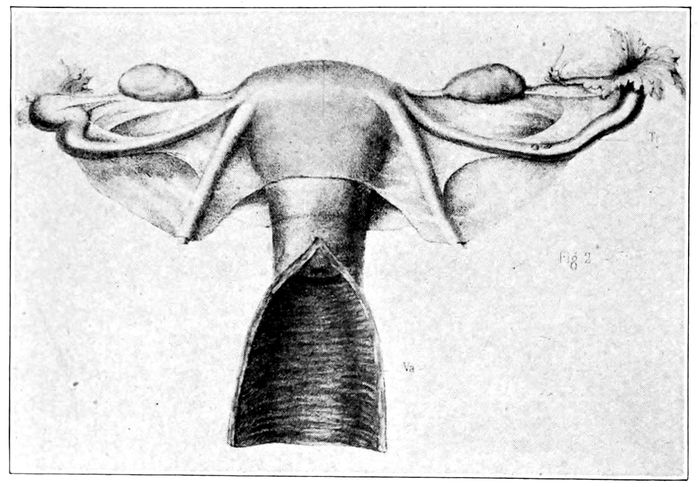

Fig. 4.—Uterus and appendages. On either side of the uterus will be seen the ovary, the fimbriated extremity of the tube, the tube, and the round ligament. The vagina lies open below. (Lenoir and Tarnier.)

Fallopian Tubes.—On either side of the upper end of

the uterus are the orifices of the Fallopian tubes, through

which the egg, escaping from the ovary, finds access to

the uterine cavity. These tubes extend outward from

the uterus about four inches, and terminate in a bell-shaped

opening with long, ragged fingers which hang

loosely down toward the ovary. The tubes are lined by

epithelial cells having hair-like projections, (ciliæ)

which wave automatically toward the uterus. Thus impelled

23by a gentle current, the egg moves definitely

along the tube toward the uterus and against this current

the spermatozoa force their way to meet and fertilize

the egg.

The Ovaries.—On either side of the pelvis, close to

the fringed end of the Fallopian tube and attached to

it, lies a small, hard, almond-shaped organ, called the

ovary. This is the intrinsic sexual gland of the female.

It contains the small cells which are to ripen and become

eggs. Each ovary is said to contain about thirty-six

thousand eggs, or ovules.